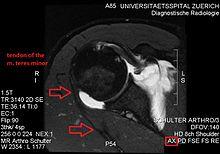

Conjoint and intact tendon disc of teres minor and infraspinatus muscle.

Intact teres minor tendon with physiologically hypointense signal.

Hyperintense, fatty degenerated teres minor muscle.

Ultrasonography is a tool to detect a fatty degenerative atrophy of the teres minor and shows in affected muscles increased echogenicity and betimes a slight reduction in muscle bulk. MR imaging helps to consolidate the diagnosis of neurogenic muscle atrophy. Extracellular edema after traumatic events causing neural damage show an increased signal intensity on T2-weighted MRI sequences and normal intensity on T1-weighted sequences. Posterior humeral circumflex artery compression and reduced blood flow in stressful arm positions and or maneuvers can be diagnosed by a Doppler ultrasonography. The nerve should be detected adjacent to the vessel. In an elevated arm position the axillary neurovascular bundle can be seen at the posterior axillary fold just before it perforates the deltoideus, while the posterior course is well visible in the neutral position. For a detailed assessment of the artery, a MR angiography is required. The major task of an ultrasonographic examination is to rule out any space occupying mass. Additional electromyography is helpful to reveal any decelerated nerve conduction velocity, and thus denervation of the concerned muscle.[6]